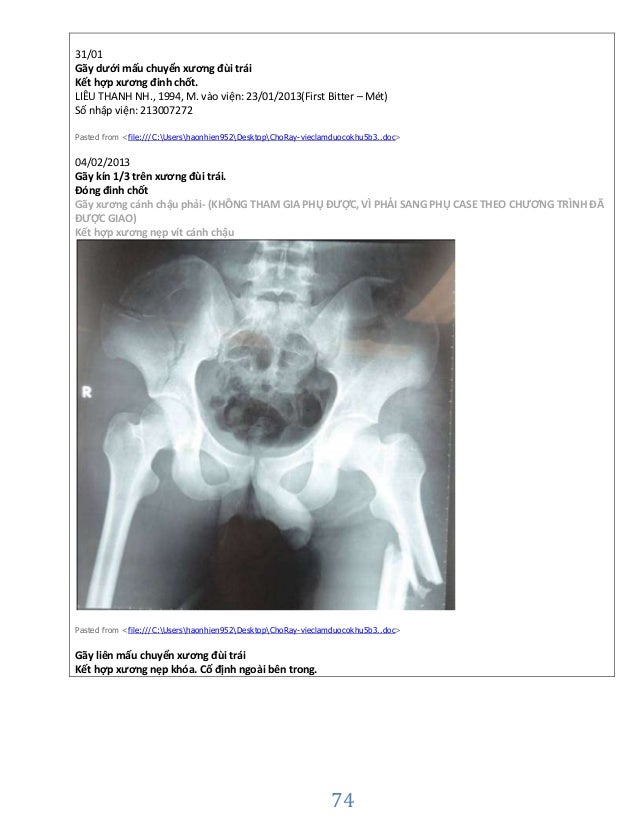

Case Ctch Phanloai Cheptuban Lau5b3

điều Trị Phẫu Thuật Gay Lien Mấu Chuyển Xương đui ở Người Cao Tuổi